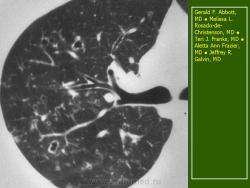

В 5 наблюдениях (21%) из больных с распространенной формой заболевания отмечались изменения в легких в виде обогащения, избыточности легочного рисунка, его деформации по сетчато-петлистому типу, очаговых теней. Корневая и медиастинальная аденопатия отсутствовали. В 1 случае в легких выявлена киста, которая периодически осложнялась нагноением (Рис. 4).

Поражение легочной ткани (рис. 22) свойственно любому возрасту. Часто больные имеют общие симптомы — лихорадку, слабость, реже — кашель, одышку, боли в грудной клетке. На рентгенограммах отмечается деформация и усиление легочного рисунка и микроузловые инфильтративные тени. Поражение костного мозга (с наличием клеток Лангерганса) сопровождается цитопенией периферической крови.

Рис. 22. Поражение легких при Лангер-гансово-клеточном гистиоцитозе.